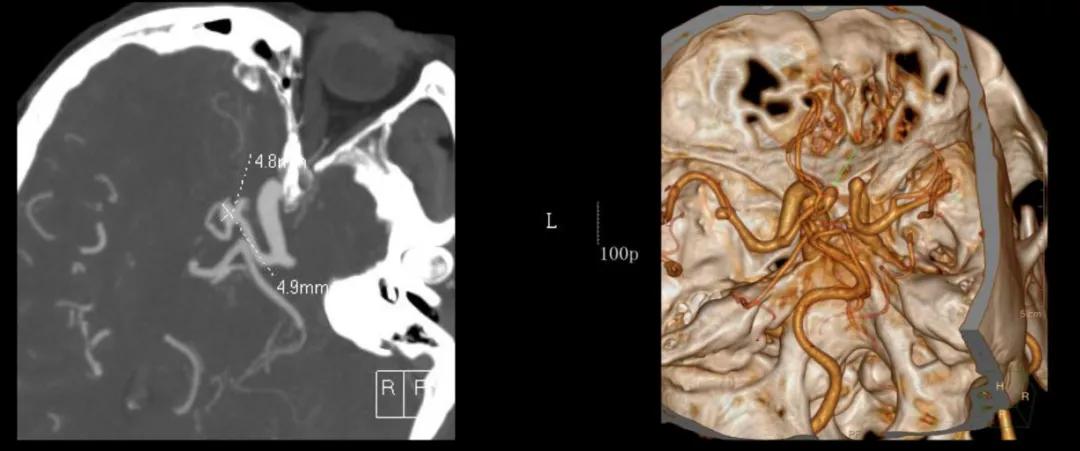

术前影像学资料:

至于林奶奶的情况,在告知家属病情、风险和可选治疗方案后,最终选择行开颅动脉瘤夹闭术。赵海康副院长、袁致海副主任医师和王悦医师根据CTA所示动脉瘤的位置及瘤颈方位,制定的手术方案为左侧翼点入路左侧大脑中动脉动脉瘤、前交通动脉瘤夹闭术,在手术团队的共同努力下,手术顺利完成。